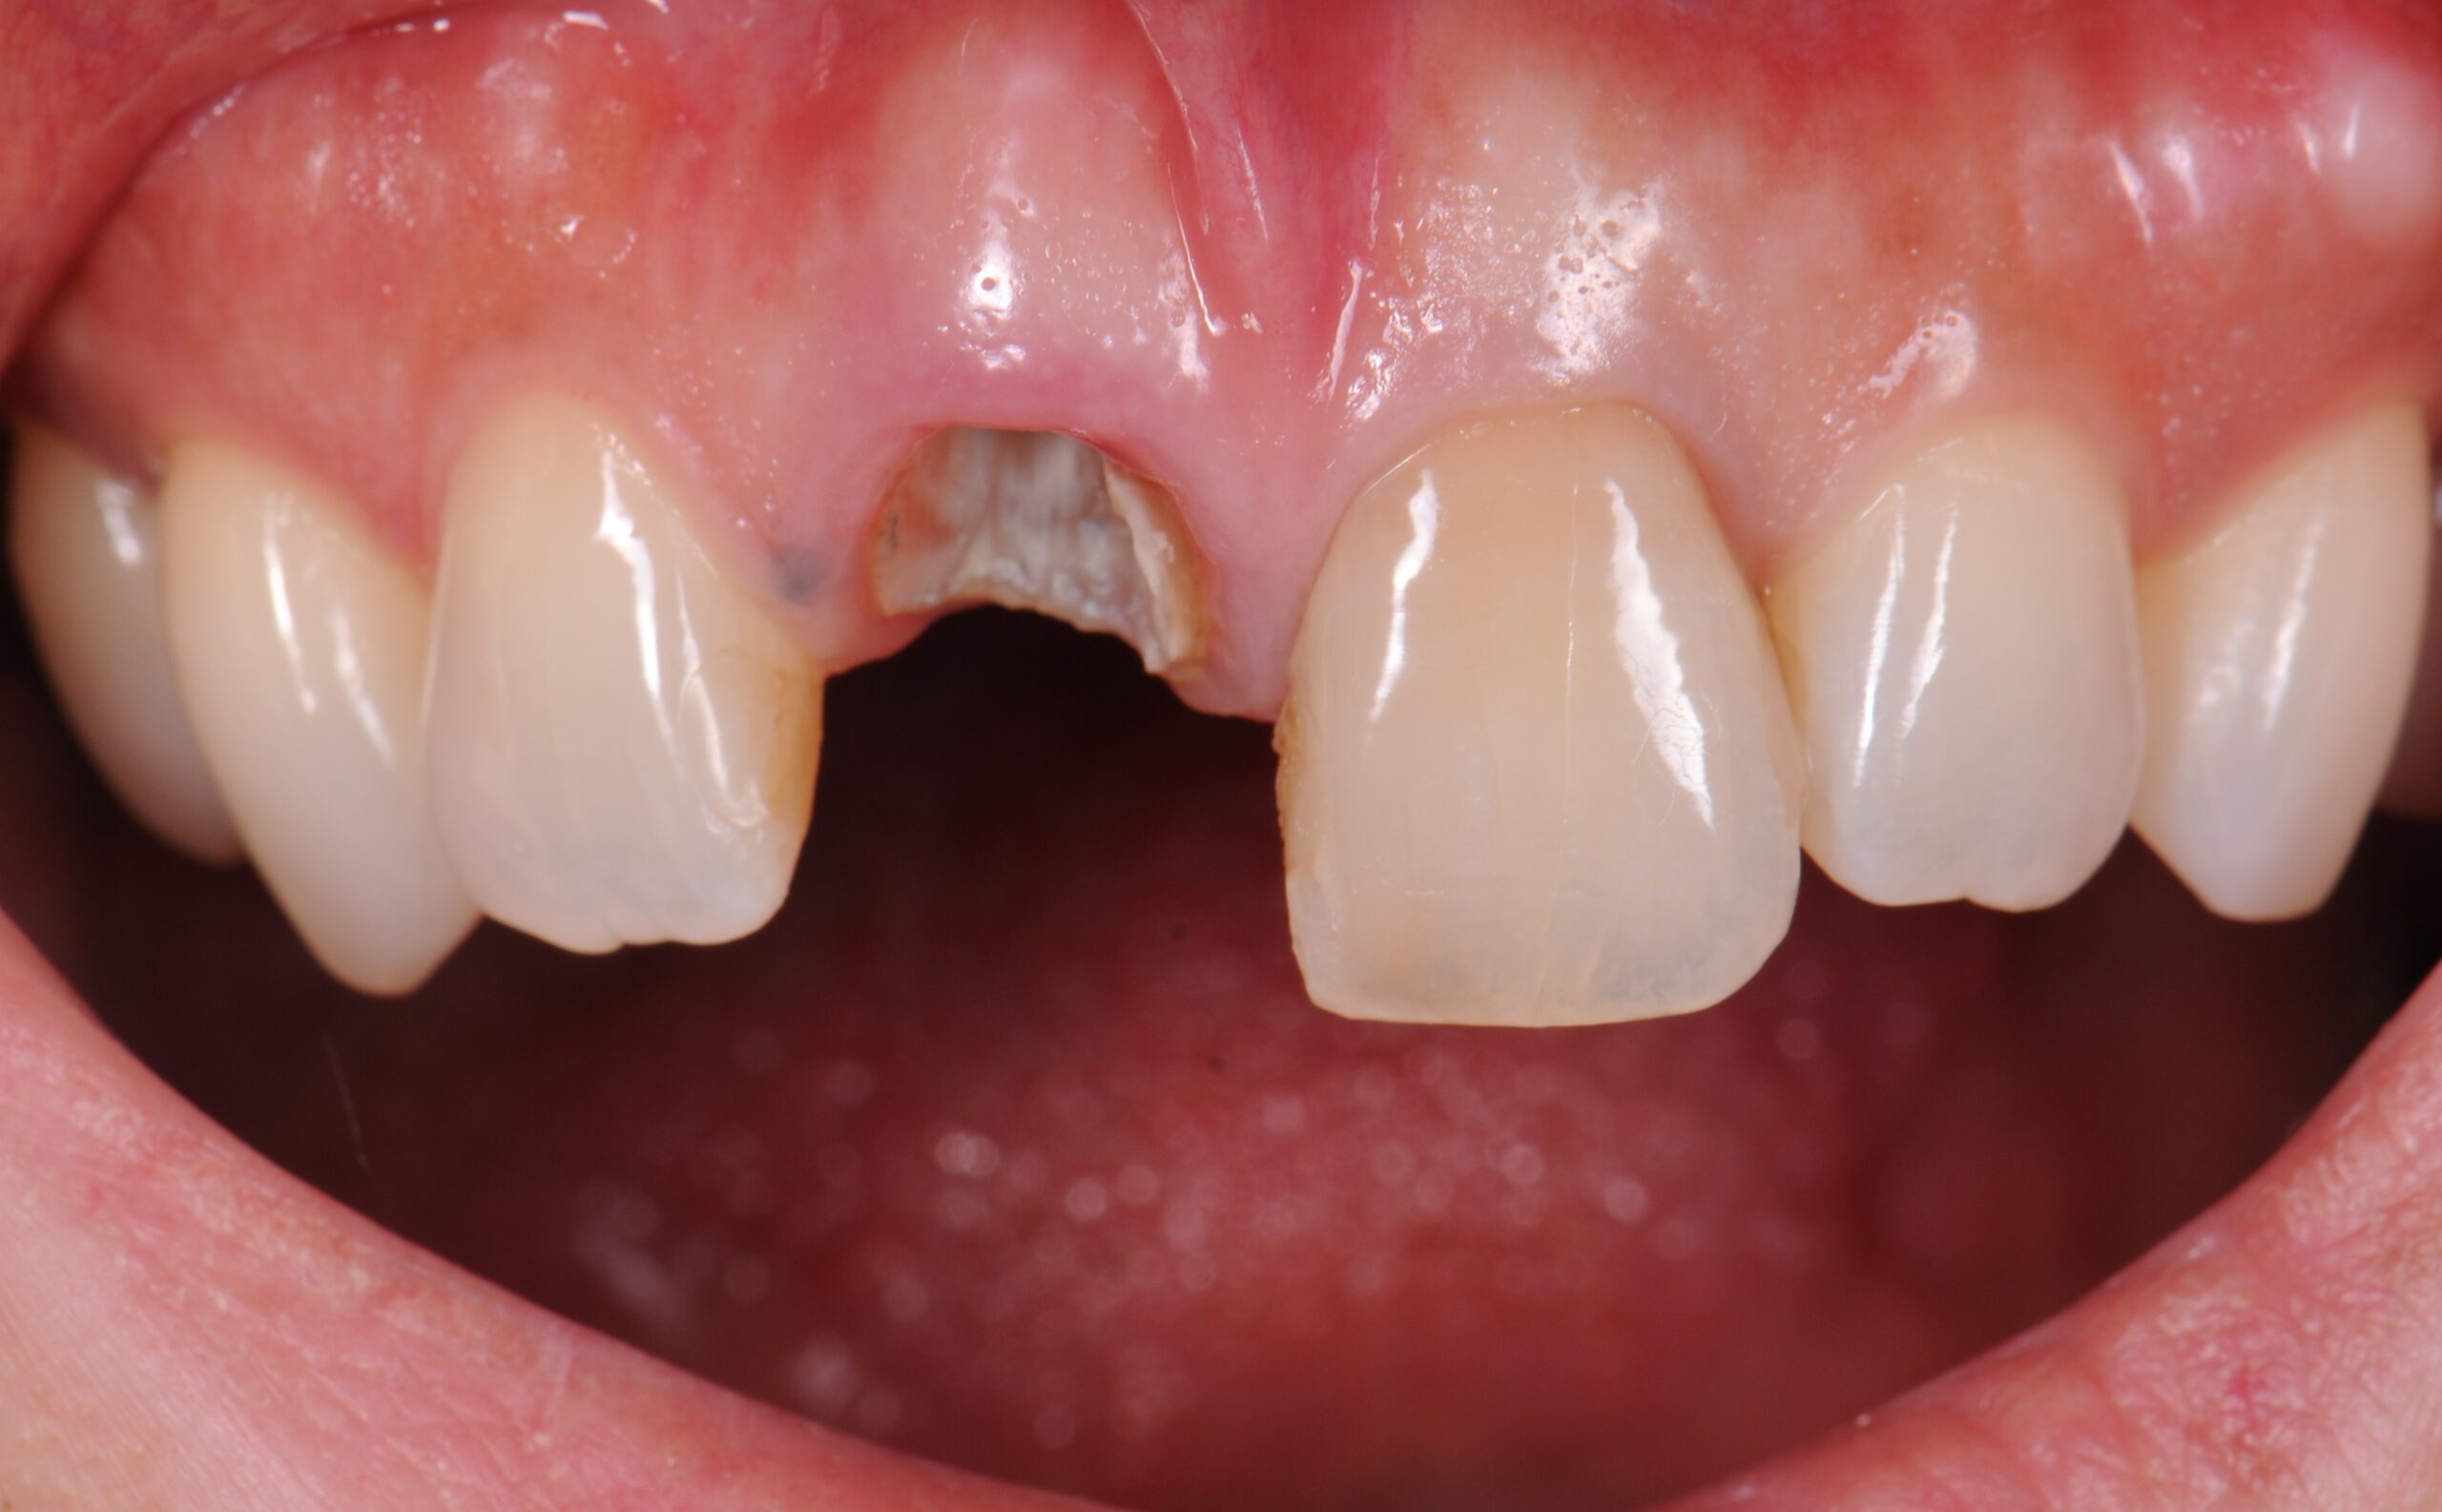

case1 症例(セラミッククラウン前歯)

治療前

| 費用(税込み) | 154,000円 |

|---|---|

| メリット・デメリット | デメリット 天然歯を削る必要がある。 |

| 治療回数 | 6ヵ月 |

| 主訴 | 前歯が黒い |